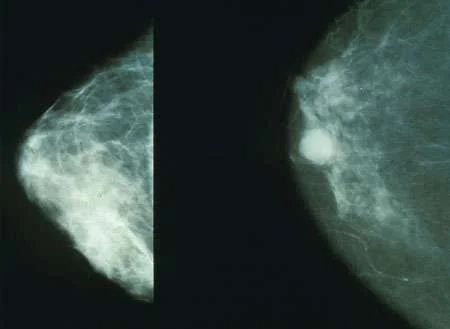

“Women who eat more high-fiber foods during adolescence and young adulthood—especially lots of fruits and vegetables—may have significantly lower breast cancer risk than those who eat less dietary fiber when young, according to a new large-scale study led by researchers at Harvard T.H. Chan School of Public Health. ”